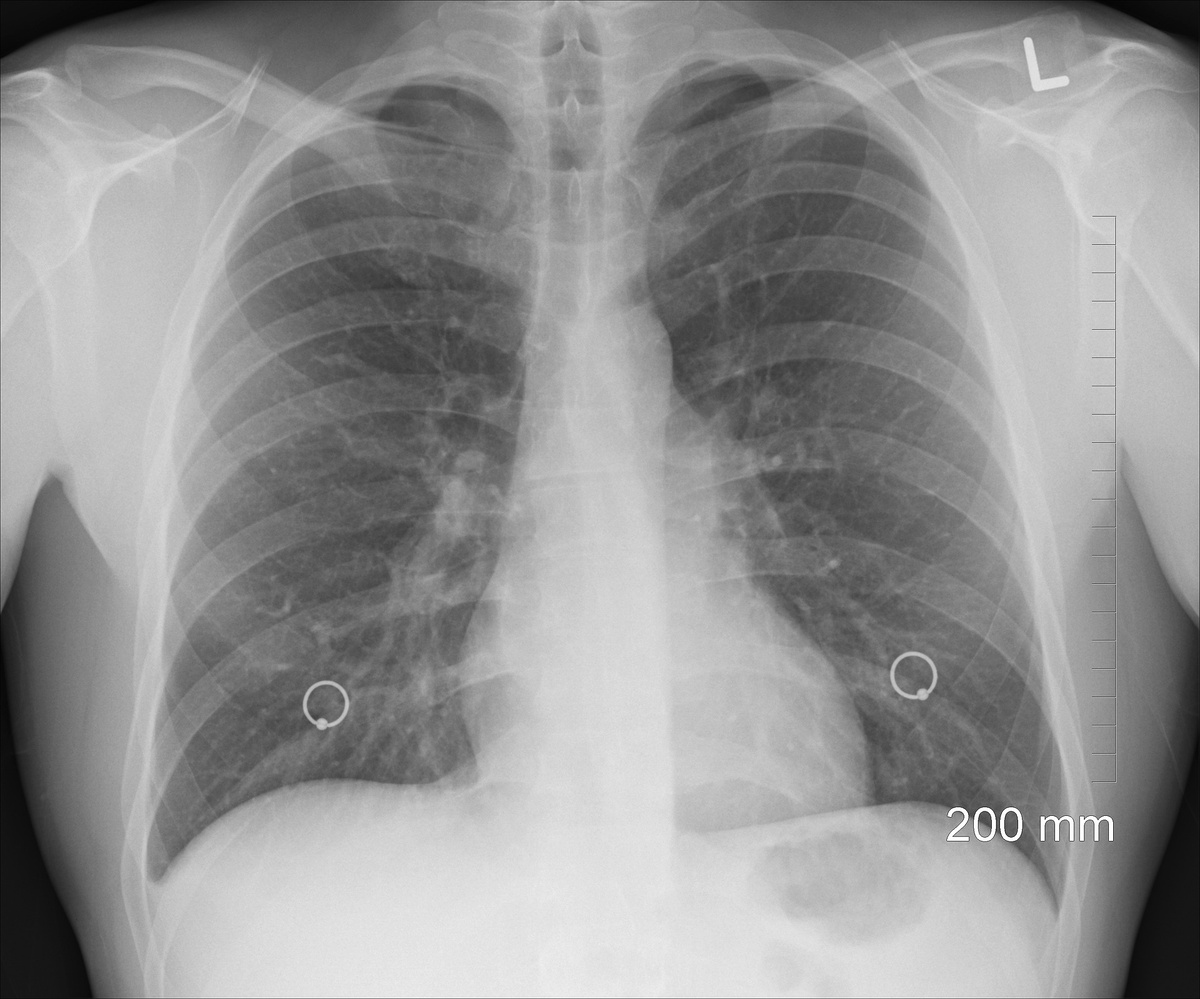

Фото с сайта pixabay.com

Работа основана на данных Британского биобанка и охватывает более 36 тысяч человек среднего и старшего возраста. Анализ показал, что участники с уровнем витамина D ниже 15 нмоль/л чаще попадали в стационар с инфекциями нижних дыхательных путей, включая бронхит и пневмонию.

По сравнению с людьми, у которых содержание витамина D превышало 75 нмоль/л, риск госпитализации у этой группы был выше на треть. Учёные также зафиксировали, что даже умеренное повышение уровня витамина D сопровождалось постепенным снижением вероятности тяжёлого течения болезни.

Исследователи отметили, что пожилые люди особенно уязвимы к инфекциям лёгких, а в зимний период риск дефицита витамина D возрастает из-за недостатка солнечного света. При этом авторы подчёркивают, что их выводы основаны на наблюдательных данных и не доказывают прямую причинно-следственную связь, однако указывают на возможную пользу поддержания адекватного уровня витамина D для профилактики тяжёлых респираторных инфекций, сообщает Газета.Ру.